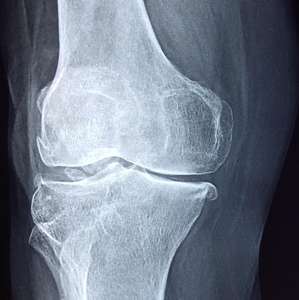

The DESIGNA study, led by Prof. McGregor and funded by Versus Arthritis, explores how diet can prevent arthritis and influence its progression. This research is of great interest to both patients and the public, as dietary changes are seen as a practical way to manage the condition. The Norfolk Arthritis Register (NOAR) has tracked individuals for over 30 years, monitoring the development of arthritis. Blood samples collected over time are being analysed for metabolic patterns that may predict rheumatoid arthritis (RA) progression. Over 200 metabolites are being analysed in more than 300 samples. By including dietary data before disease onset, the study aims to identify how diet could reduce the risk of RA onset and progression.